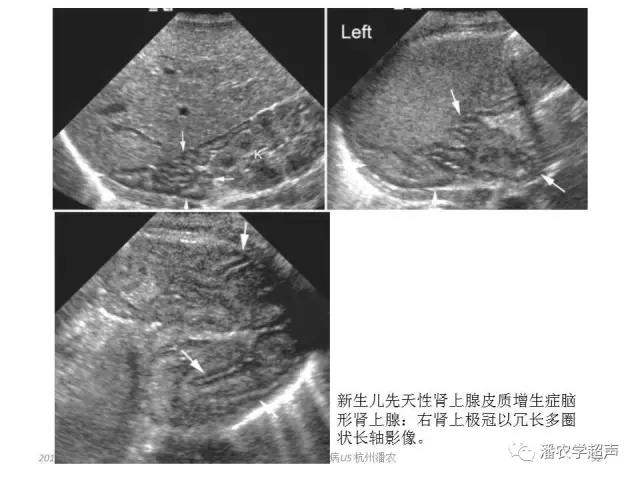

先天性肾上腺增生

一种因肾上腺皮质内酶缺乏导致的隐形遗传病。可导致女性男性化或男性早熟,是女性假两性畸形的最常见原因。超声可明确其体内是否存在女性内生殖器官(子宫和卵巢)。由于阴道异常或狭窄导致宫腔内少量积液。